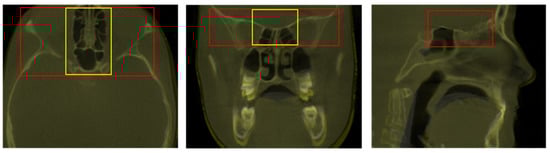

The pairs of DICOM datasets, acquired at two different time points (T0 and T1), were imported into the software. For the purpose of this study, three superimposition reference areas were compared. The first area, considered as the reference method, was the total anterior cranial base (TACB), the second area was an extended version of the middle anterior cranial base area (EMACB), and the third area was limited to the middle anterior cranial base area (MACB), as described previously [23,25]. All areas include the midline structures of the anterior cranial base that are the standard structures used to assess craniofacial changes [3]. In order to define these areas, the selection frame tool of Dolphin software was used, provided under the option for the manual superimposition of volumes. The anterior–posterior and superior–inferior borders of the TACB and the EMACB areas were identical and delineated by the posterior wall of sinus frontalis (anteriorly), the middle of sella turcica (posteriorly), and a line 2–4 mm inferiorly to the floor of sella turcica. The height of the frame was 3–4 cm, and this defined the superior border of the reference area. The two reference areas differed only in their lateral extensions. The TACB extended laterally to include the entire width of the anterior cranial wall, as described in previous work [20,21,22,23], while the EMACB extended laterally to include the width of the anterior clinoid processes of the sphenoid bone. The MACB area was defined similarly anteroposteriorly, extended less laterally to include only midline structures, and was approximately 1 cm shorter vertically. This area has been thoroughly described and tested previously [23,25], and thus it will be presented here briefly, to allow direct comparison to the two primary study methods (TACB and EMACB). The TACB and EMACB frames are presented in Figure 1.

Visual assessment of the 2D DICOM images of all 15 cases, at all three planes of space, as observed on the screen, showed adequate overlap of the midline anterior cranial base superimposition reference structures that are considered stable during growth, for both TACB and EMACB techniques (Figure 1). The findings were confirmed during the repeated assessments by the same operator. Thus, TACB and EMACB methods showed perfect reliability, in contrast to reduced reliability of MACB that has been published previously [23].

Figure 1. Definition of the Total Anterior Cranial Base area (TACB) (in red) and the Extended Middle Anterior Cranial Base area (EMACB) (in yellow) depicted on T0–T1 volumes, following TACB superimposition. On the right image, the EMACB frame is not visible because it is identical to the one of TACB.